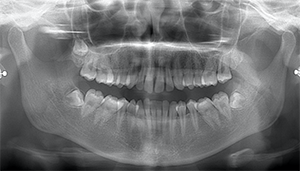

右下奥歯が痛い症例

- 抜歯前写真(レントゲン)

- 抜去歯の写真(CT画像)

| 抜歯内容 | レントゲン上で右下の親知らずが大きく虫歯になっており、斜めに生えていることもあり患者様の希望により抜歯することとなりました。 当日は痛みがあったため抗生剤と鎮痛剤にて炎症を抑え、後日歯ぐきを切開し、抜歯を行いました。 レントゲン上でも分かるように親知らずの根が二つに分かれており根が折れてしまう可能性がありましたが、このケースでは事前にCTを撮影し、歯の位置、根の方向を確認していたため根が折れることなく抜歯ができました。 術後数日は腫れと痛みがありましたが、薬の服用で抑えることができ、1週間後の糸取りの際には痛み、腫れともになくなっていました。 |